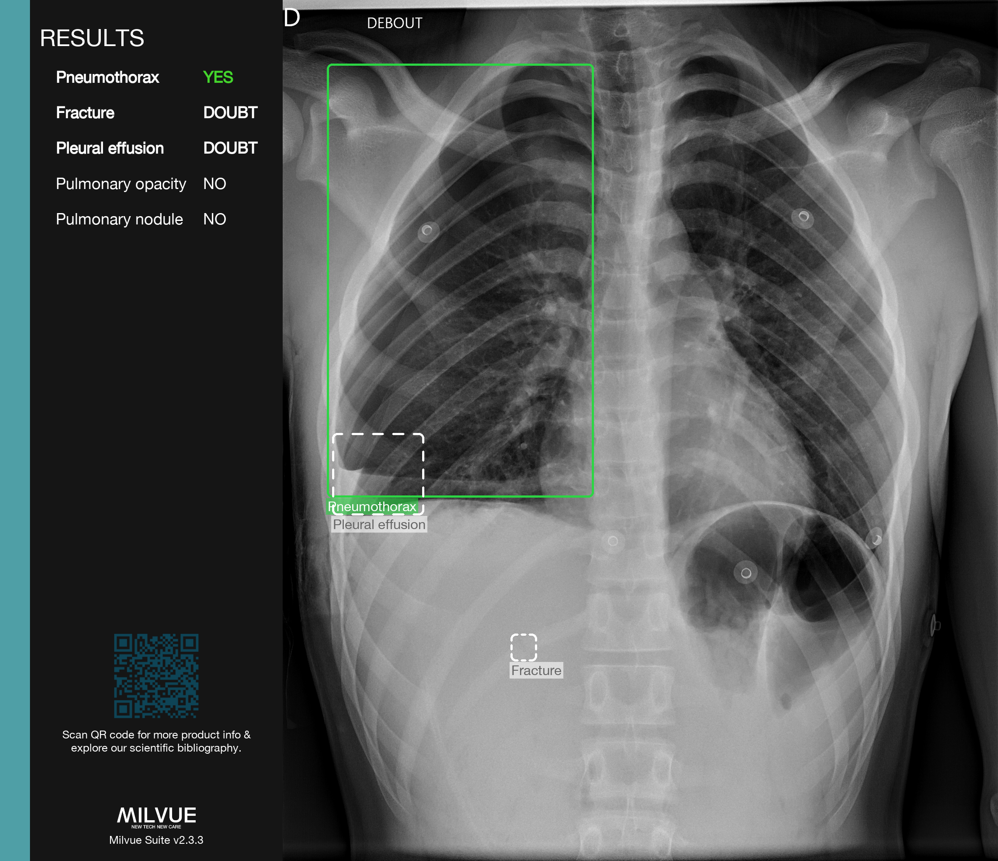

The Lenval Foundation is taking a new step in medical innovation by integrating artificial intelligence (AI) solutions from Milvue into its imaging center. This advanced technology optimizes the detection of fractures, pulmonary nodules, pleural effusions, and enables the rapid execution of various orthopedic measurements in standard radiology, including EOS exams.

With the integration of Milvue’s AI solutions, radiologists, emergency physicians, and orthopedic specialists at Lenval now have an intelligent co-pilot to assist them in analyzing medical images.

As soon as the images are acquired, artificial intelligence instantly analyzes them, identifying the presence or absence of pathologies while automatically generating precise anatomical measurements.

By leveraging AI, the medical teams at Lenval’s imaging center benefit from valuable support in their daily practice, enhancing the care of young patients while improving diagnostic accuracy and reliability. Milvue claims to improve diagnostic sensitivity for pediatric fractures by 20%, reduce emergency room wait times, and automate certain orthopedic measurements to increase productivity.

Milvue’s AI solutions support the entire diagnostic workflow for radiologists, emergency physicians, and orthopedic specialists, offering advanced tools for prioritization, detection, measurement, and automated reporting.